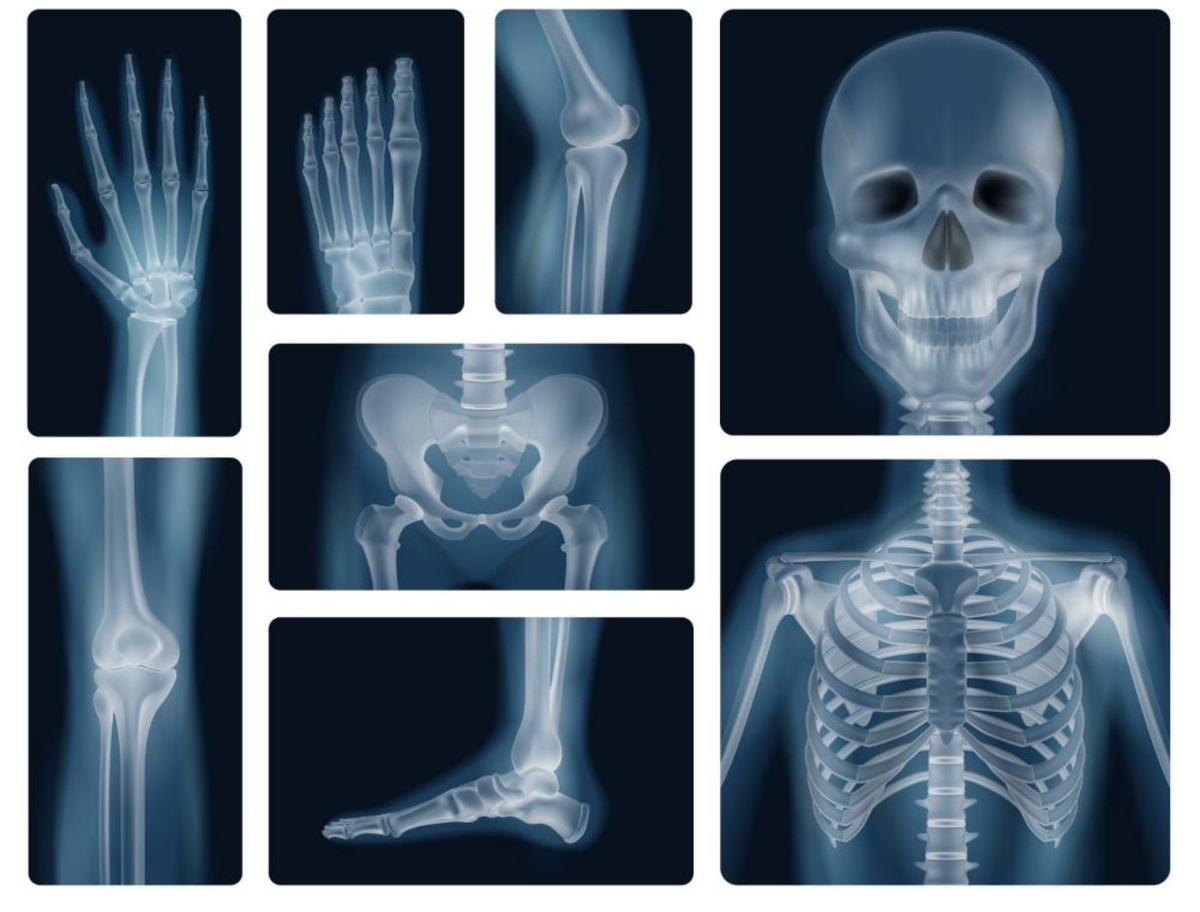

О ЛУЧЕВЫХ И ПРОЧИХ МЕТОДАХ ВИЗУАЛИЗАЦИИ В МЕДИЦИНСКОЙ РЕАБИЛИТАЦИИ

Вильгельм Рентген своим удивительным открытием расширил горизонты возможностей большинства медицинских специальностей, как в плане диагностики, так и лечения. Особое значение рентгеновские лучи имеют в областях, связанных с опорно-двигательной системой. Наряду с травматологами кланяются знаменитому физику специалисты по спортивной медицине и медицинской реабилитации. В этих сферах рентгенологические исследования позволяют не только диагностировать воспалительные, посттравматические и дегенеративные изменения в организме, но и контролировать эффективность восстановительного процесса.

Представьте, что каждый снимок — это подробная карта, которая помогает понять, какие структуры организма требуют особого внимания, а какие уже на пути к заживлению. Рентгенография, как классический и доступный метод, помогает видеть состояние костей, суставов и позвоночника, выявлять переломы, вывихи, сколиоз и плоскостопие, что крайне важно для разработки планов реабилитации и оценки динамики восстановления.

Важной особенностью рентгеновских исследований является способность быстро и чётко визуализировать костные изменения, благодаря естественной контрастности тканей с разной плотностью. Это значит, что врач-реабилитолог может оперативно получать важную информацию для коррекции лечебных мероприятий. Например, рентген с функциональными пробами позвоночника позволяет оценить подвижность и состояние межпозвоночных дисков, что помогает назначить правильную терапию и физиопроцедуры.

Один из наиболее частых случаев — контроль заживления переломов костей. Так, после перелома конечности, рентгенография помогает точно определить положение костных отломков и оценить степень сращения кости. Это особенно важно в первые месяцы реабилитации, чтобы своевременно скорректировать методы иммобилизации и физической нагрузки. Если увидеть смещение или несращение, врач может изменить лечение или рекомендовать оперативное вмешательство.

Еще один пример — использование рентгена для диагностики и контроля заболеваний позвоночника. При сколиозе или остеохондрозе рентген помогает увидеть степень искривления, состояние межпозвонковых дисков и костных структур. Это позволяет врачу определить, какие методы ЛФК, массажей и физиотерапии будут наиболее эффективными, а также контролировать динамику исправления позвоночника во время курса реабилитации. Аналогично, при травмах и воспалениях суставов рентгенография выявляет вывихи, подвывихи, артрозные изменения и помогает скорректировать нагрузки и поддерживающие процедуры.